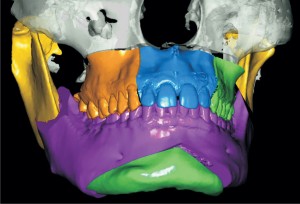

Hoje, o doutor explica que basta realizar, no paciente, uma tomografia tridimensional de sua face. “Depois, inserir no software que foi criado para o planejamento virtual calculando todas as medidas e desenhando o que o paciente necessita . Eu consigo operar o paciente diretamente na tela e criar os guias para o intra-operatório”, completa.

O primeiro passo é individualizar o exame do paciente com sua fotografia, fazendo uma análise facial completa. Depois, através da tomografia, é possível avaliar em três planos diferentes do espaço do paciente, avaliando as discrepâncias dentárias e esqueléticas, localizando assim a origem de todo o problema que afeta o paciente em questão.

Após a análise tomográfica e a cirurgia virtual conseguimos avaliar qual a melhor oclusão e relação das bases ósseas. O método virtual é ainda mais eficaz para casos de assimetrias da face, harmonizando as discrepâncias de deformidades dento-faciais.